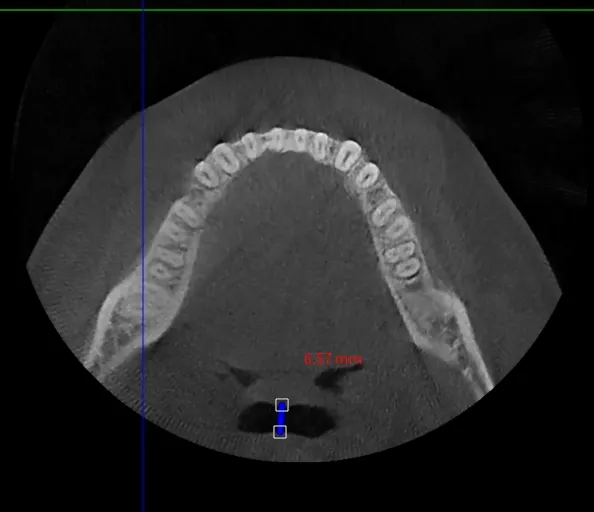

When necessary, we diagnose additional anatomical issues through neck CT (Airway CT) scans.